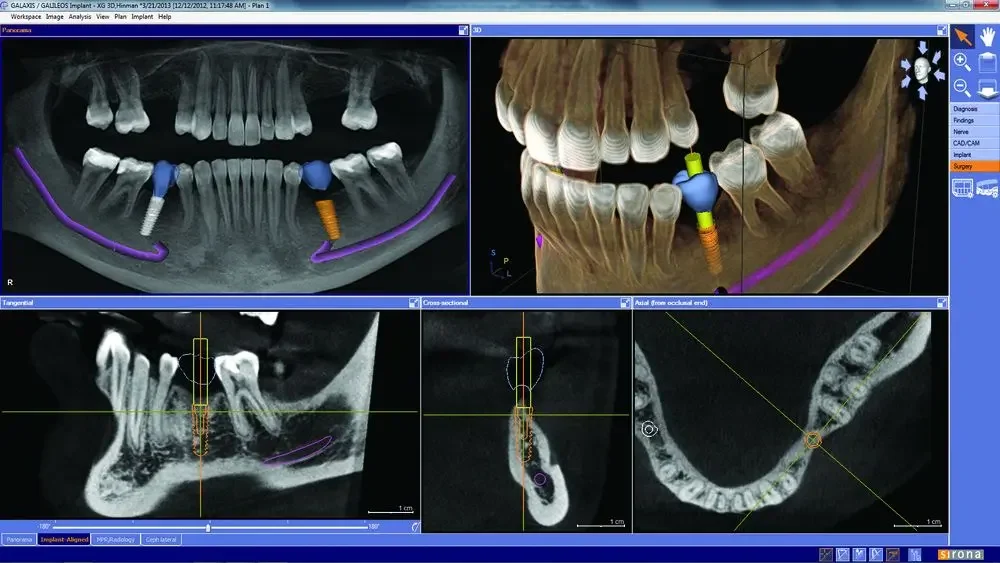

Digital implant planning

Using advanced digital planning software, we can map out implant placement before treatment begins. This allows for optimal positioning, improved stability, and predictable results.

Why it matters to you: safer procedures and restorations that look and feel natural

Galileo digital implant planning screen